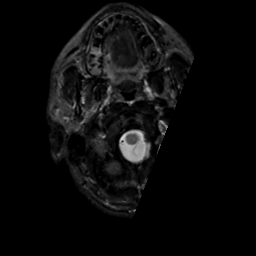

MR Study #5, March 10, 1991 -- Slice #3

[Home][Help][Clinical][Tour 1][Tour 2] Slice 3